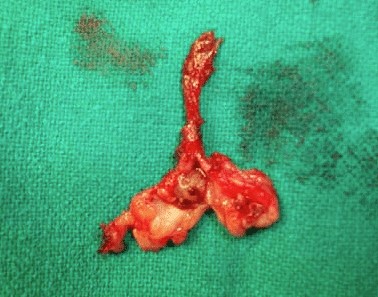

- Eksisi bedah duktus yang terkena dengan lesi intraductal yang dikenal sebagai Microdochectomy

Probe lakrimal digunakan untuk menemukan saluran dengan mengeluarkan dan seluruh saluran akan diangkat melalui pembedahan untuk pemeriksaan histopatologis (HPE).

Seluruh saluran payudara diangkat yang menunjukkan massa intraductal di dalamnya